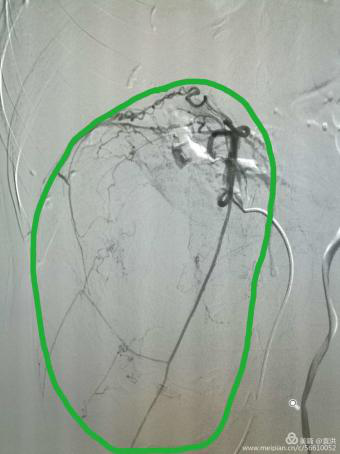

介入治疗中“经导管栓塞术”是通过阻断血管内血流而达到治疗各种类型的大出血、血管异常或者为丰富血供的病变预栓塞,为特大外科手术创造无出血的条件。术前DSA引导下行病变血管栓塞,可有效地减少术中出血, 使手术视野更清楚, 肿瘤更易于暴露, 使邻近的解剖结构更容易显露, 为顺利、彻底切除肿瘤创造了条件。术中出血少,也有利于患者术后的恢复。

(介入DSA下造影提示:肿瘤供血丰富

存在广泛的侧枝血管供血)

(介入栓塞后,肿瘤血液供应完全阻断

大大降低了手术出血风险)